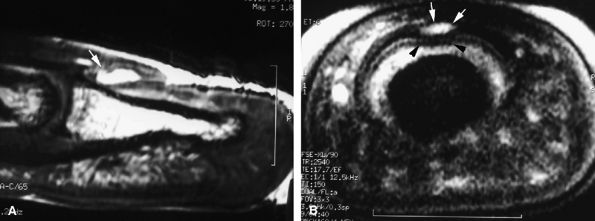

FIGURE 11.20 ● Acute injury of the radial collateral ligament (RCL) of the PIP joint of the fourth finger. Coronal (A) and axial (B) post-contrast fat-suppressed T1-weighted images displaying distal avulsion of the RCL with a proximal retraction (black arrows). The retinacular apparatus is displaced (arrowheads) with periligamentous edema. The ulnar collateral ligament is also identified (white arrows).